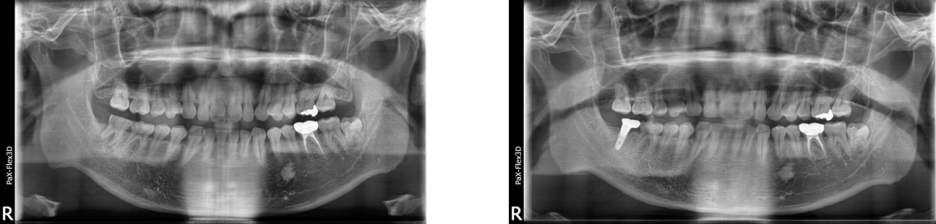

49세 남성

(전) 2021-08-18 (후) 2022-09-14

치아 안쪽이 썩어

발치 후 임플란트 하신 환자분 사례